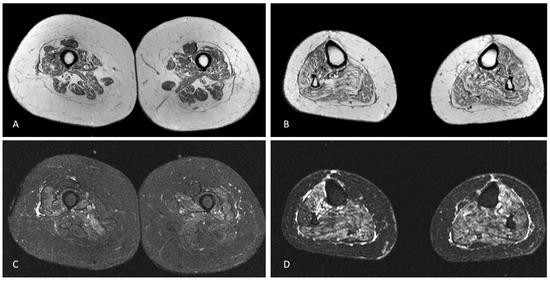

Blood tests were unremarkable, including sedimentation rate, serum creatine kinase (CK) and autoimmunity screening (anti-nuclear, anti-double stranded DNA, ANA screening, lupus anticoagulant, anti-cardiolipin, anti-β2-glycoprotein-I, anti-Jo-1, anti-Mi-2 and anti-SRP antibodies). Serology for HIV 1/2, hepatitis B/C, Lyme and syphilis were negative. CSF analysis was unrevealing, including neurotropic virus panel and anti-neuronal antibodies (anti-Hu, anti-Yo, anti-Ri, anti-CV2, anti-SOX1 antibodies). Sensory nerves conduction studies were normal. Motor responses were absent (lower limbs) or of small amplitude (upper limbs), but conduction velocities were normal in the forearms bilaterally. Needle sampling showed abnormal spontaneous activity (fibrillation potentials/positive sharp waves) and mainly myopathic potentials (short duration, small amplitude and polyphasic) in biceps brachii, first dorsal interosseous, vastus medialis and tibialis anterior, bilaterally. However, in these muscles some large amplitude motor unit potentials with increased firing rate were observed. Sternocleidomastoid and genioglossus muscles were considered normal. Brain and spinal cord MRI were normal. Muscle MRI of the lower limbs showed symmetrical signs of fatty degeneration, with major signal increase in fat suppression sequences (Figure 1). Right deltoid biopsy disclosed mixed myopathic (type 1 fibre predominance) and neurogenic (type-grouping) findings. There were no rimmed vacuoles, cytoplasmic inclusions or inflammatory infiltrate. Dystrophin (Dys 1, Dys 2 and Dys3 fractions), sarcoglycans (α, β, δ and γ) and laminin M-chain (merosin) expression was normal. Sarcolemma MHC class I staining was normal. One year later, a clear neurogenic pattern was also disclosed in sternocleidomastoid and genioglossus muscles, with large motor units, complex and unstable, with increased firing rate.

Figure 1. Axial T1-weighted MRI of the mid-thighs (A) and middle third of the legs (B) demonstrating mild, symmetric muscular fatty atrophy of the quadriceps muscle and the hamstring muscles and moderate fatty atrophy of all leg muscles. Axial STIR-weighted images of the thighs (C) and legs (D) at the same levels of A and B showing mild oedema of vastus medialis, vastus intermedius, vastus lateralis and, to a lesser degree, of the hamstring muscles in the thighs and severe oedema of all leg muscles.